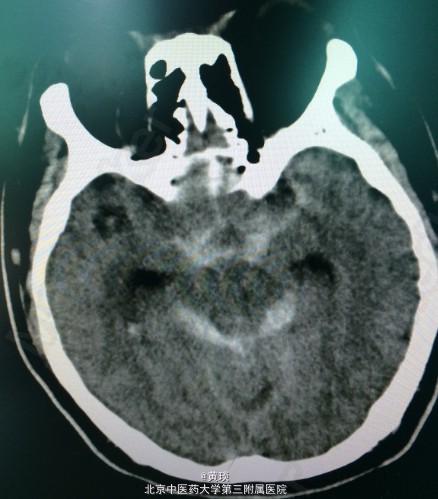

患者男,46岁,主诉:左侧肢体麻木伴进行性意识障碍5小时。 现病史:患者5小时前无明显诱因出现左侧肢体麻木,伴头痛,约4小时前出现呕吐,为喷射性,呕吐物为胃内容物,逐渐出现意识障碍,无肢体抽搐,约3小时前出现小便失禁,言语模糊。120送我院急诊就诊,行CT检查提示脑室内出血,于急诊给予保守治疗,患者意识障碍加重,预手术治疗收入院。

辅检:头CT示:右侧侧脑室内高密度影,脑室铸型(脑室铸型就是出血量过大,填满脑室,开起来就好像灌注雕塑一样)

初步诊断: 脑出血 脑室铸型 处理:颅内血肿清除术